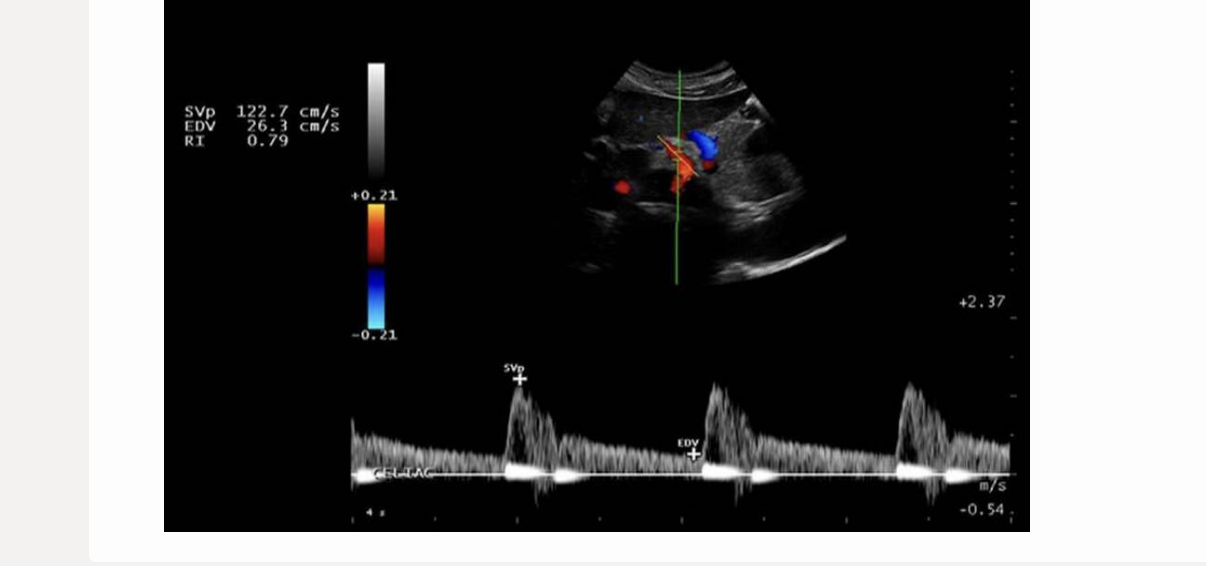

which describes a normal renal artery waveform

.

a) low resistance w/increased diastolic flow

b) increased diastolic flow reversal

c) biphasic w/mild diastolic flow reversal

d) pulsus alternans [methodical variation in peak vel on every other beat]

a. low resistance w/increased diastolic flow